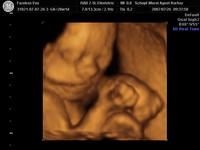

Nagyon helyes az UH képen a kis krumpliszsákotok! :D

Csodaszép a Krumpliszsákod! :D

Estrella nagyon jó ez a kép Krumpliszsákról :wink: !

Édes ez a kis krumpliszsák!